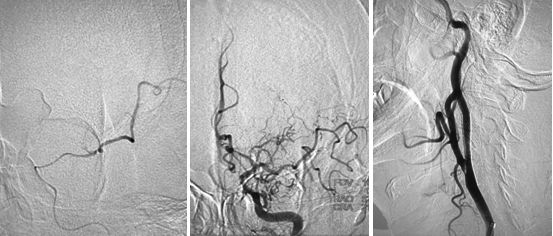

在路径途指导下,将微导丝(Transcend)、微导管(Rebar 027)沿导引导管送至左侧大脑中动脉M2段,撤出微导丝,经微导管造影,造影证实微导管位于真腔内,大脑中动脉远端血管通畅,将取栓支架Solitaire AB (6x30mm) 送至血栓处,释放取栓支架,静置5分钟后取出支架,可见支架内大量血栓,复查造影提示左侧大脑前动脉、左侧大脑中动下干通畅,左侧前大脑前动脉可向左侧大脑中动脉代偿供血,(图7)此时患者右侧肢体无力症状明显好转,仍有不完全混合性失语,视察10分钟后复查造影提示血流仍然通畅,颈动脉支架处血流通畅,遂结束手术,继予以替罗非班抗栓治疗。

图7